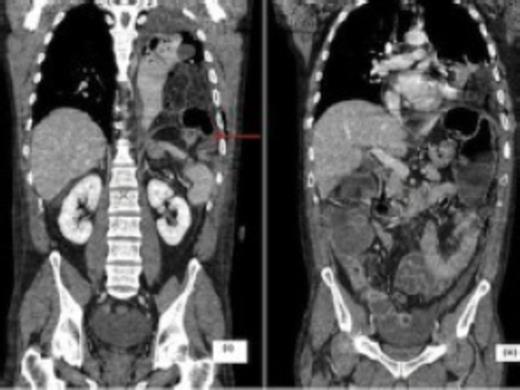

The CT scan showed a left-sided hydropneumothorax with herniation of the omentum and transverse colon through a defect in the postero-lateral left hemi-diaphragm with dilatation of the proximal colon (Fig. 2). Laparotomy confirmed an obstructed diaphragmatic hernia with perforation of the transverse colon into the left hemithorax cavity. The caecum was grossly distended with gangrenous patches and an extended right hemicolectomy with end-ileostomy was performed. Splenectomy was also required for a capsular tear. The left hemithorax was lavaged copiously and a thoracostomy tube placed.

CT scan coronal images depicting the diaphragmatic defect (arrow) with herniation of mesentery and bowel into the left hemithorax (i) and large bowel dilatation proximal to the defect (ii)